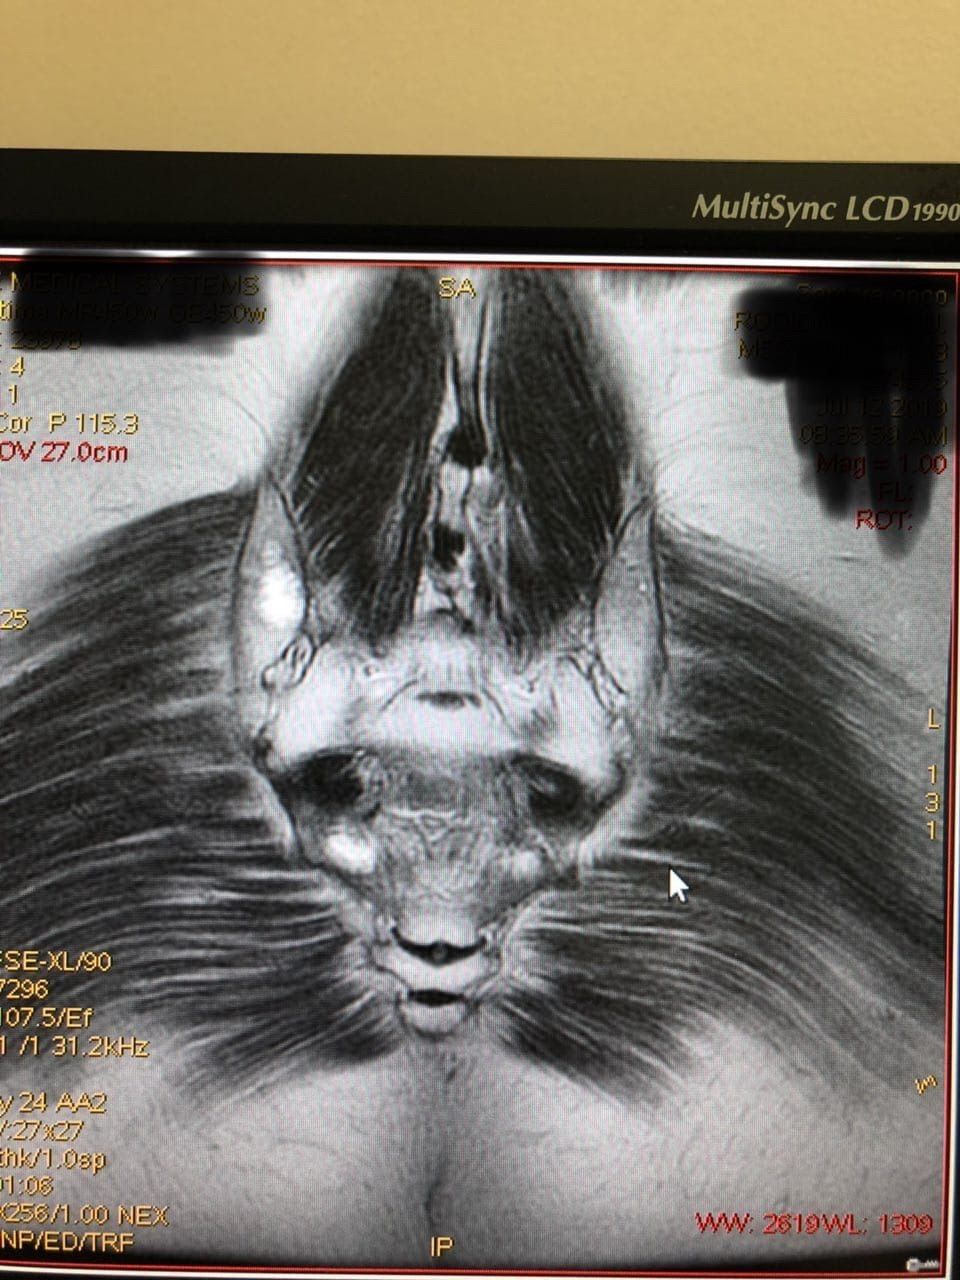

Шикарную аневризму вам на ночь глядя (или с утра пораньше кому-то). Коронал натив ➡️ аксиал натив ➡️контраст истинного просвета ➡️ контраст ложного просвета.